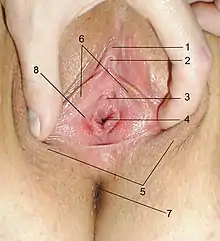

Vaginal opening and hymen

The vaginal opening (also known as the vaginal introitus)[20] is at the posterior end of the vulval vestibule, behind the urethral opening. The opening to the vagina is normally obscured by the labia minora (inner lips), but may be exposed after vaginal delivery.[10]

The hymen is a thin layer of mucosal tissue that surrounds or partially covers the vaginal opening.[10] The effects of intercourse and childbirth on the hymen vary. Where it is broken, it may completely disappear or remnants known as carunculae myrtiformes may persist. Otherwise, being very elastic, it may return to its normal position.[21] Additionally, the hymen may be lacerated by disease, injury, medical examination, masturbation or physical exercise. For these reasons, virginity cannot be definitively determined by examining the hymen.[21][22]